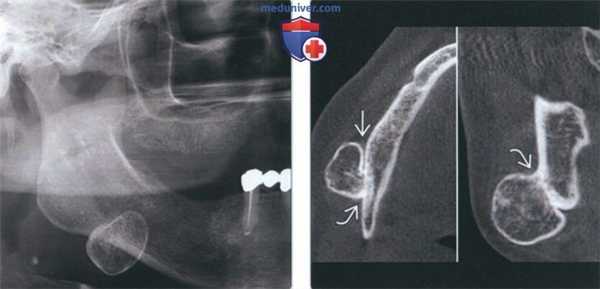

(Слева) На панорамной рентгенограмме у юноши 17 лет в отсутствие каких-либо симптомов определяется образование смешанной плотности в области 1-го моляра нижней челюсти справа -остеобластома (ОБ), очень близко напоминающая цементобластому. Видимая вершина корня отличительный признак. Нижнечелюстной канал смещен книзу.

(Справа) На панорамной рентгенограмме у девочки 13 лет определяется плохо отграниченное просветление под слегка смещенными корнями премоляров нижней челюсти слева и между ними.

2. Рентгенография при остеобластоме челюсти:

• Интра- и экстраоральная рентгенография:

о Опухоль различной рентгеновской плотности:

- Опухоль, вплотную прилежащую к корню зуба, можно спутать с цементобластомой или периапикальной патологией, особенно при наличии болевой симптоматики:

Проба на жизнеспособность и отсутствие явной причины (кариес/перелом) помогают исключить патологию пульпы

о Возможно смещение или резорбция корней зубов

3. КТ при остеобластоме челюсти:

• КЛКТ и КТ в костном окне:

о Может обнаруживаться вздутие

(Слева) На КЛКТ(профильный срез) у этой же пациентки структура ОБ выглядит зернистой. Обратите внимание на поражение язычной и щечной кортикальных пластинок в отсутствие вздутия.

(Справа) На аксиальной КЛКТ у этой же пациентки определяется поражение кортикальных пластинок опухолью с однородной зернистой структурой. ОБ челюстей обнаруживаются преимущественно в теле нижней челюсти; их рентгеновская плотность варьирует (рентенонегативное образование-опухоль смешанной плотности с множественными кальцинатами).